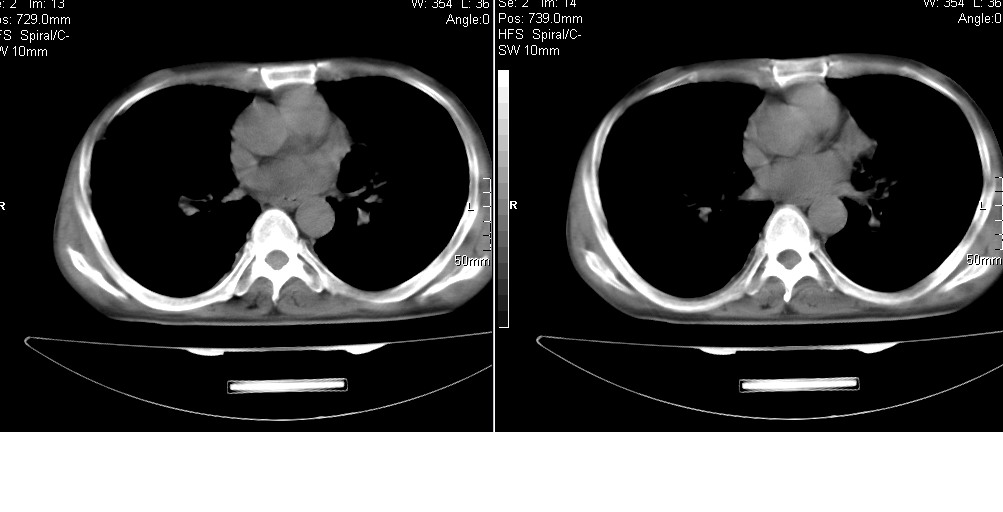

以下是引用光线在2008-5-6 18:36:00的发言:[br]双肺结核(左上肺空洞形成)、间质性改变合并感染,右肺大泡;右侧胸膜增厚。

以下是引用zsl6918在2008-5-7 1:54:00的发言:[br]首先肺泡蛋白质沉着症,其次考虑机遇性感染。